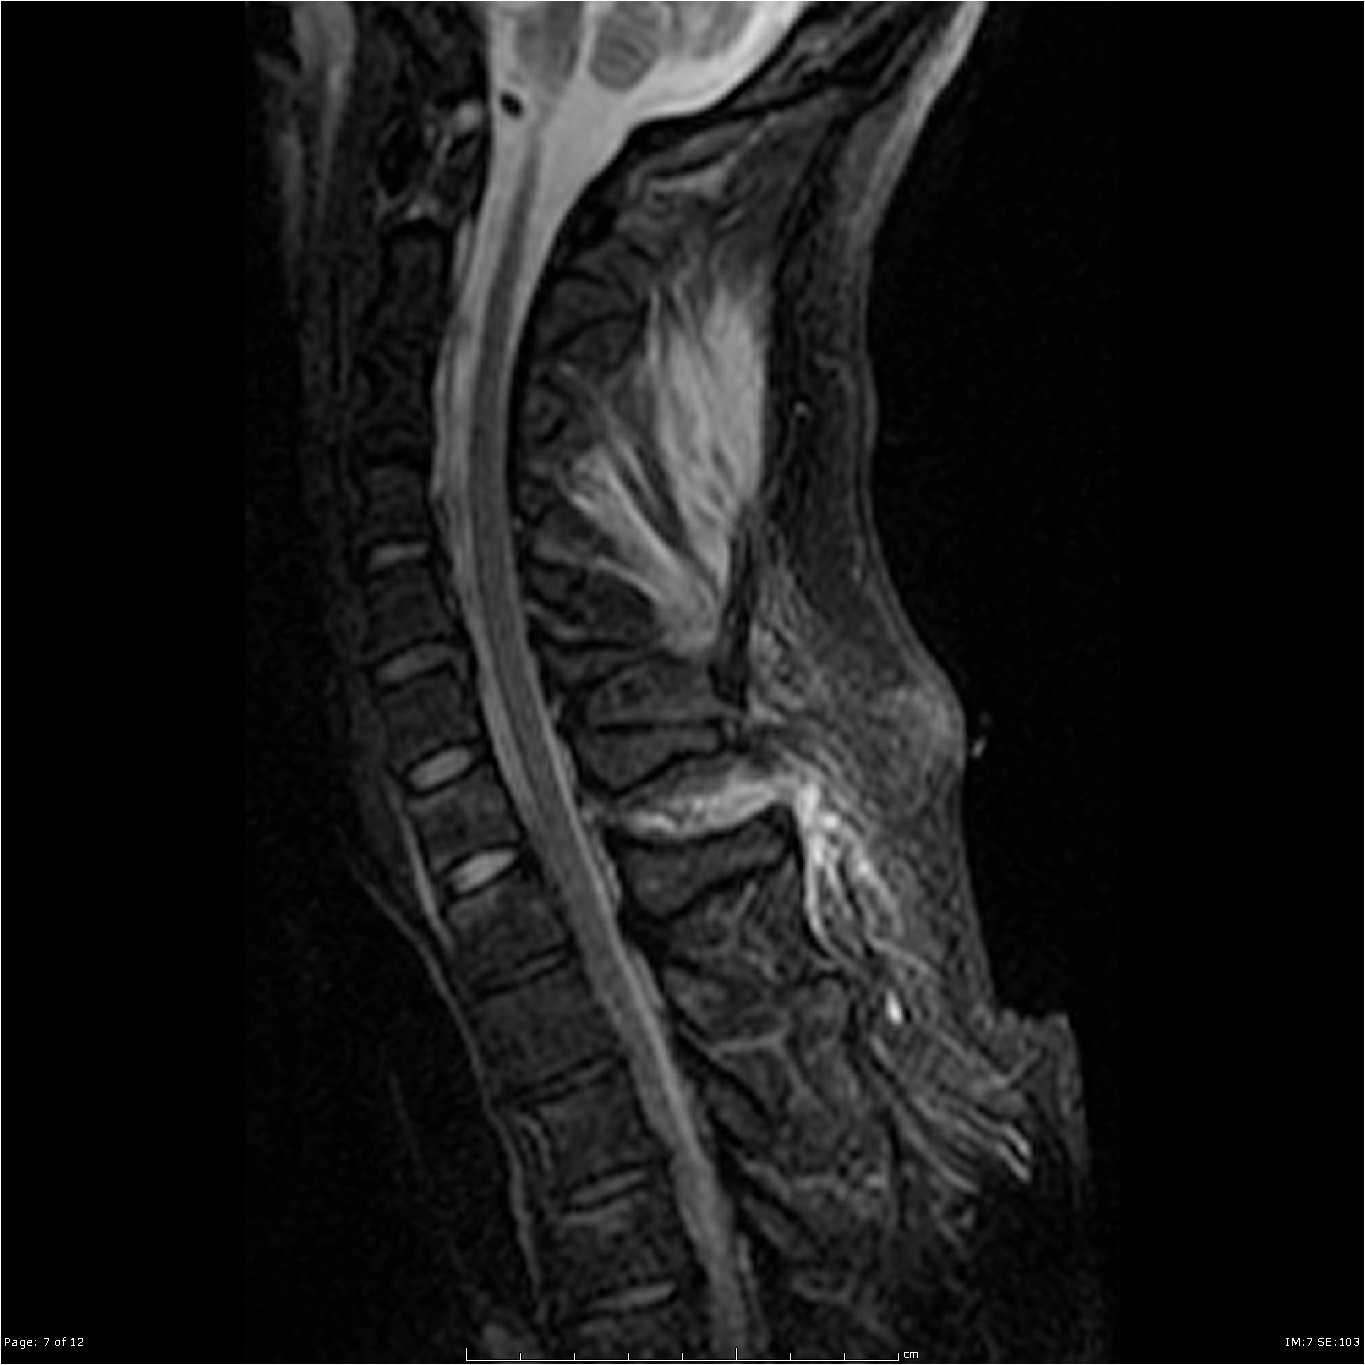

MRI of the neck showing Ligamentum flavum tear from C7-T1 not seen on CT

Soft tissue or ligamentous injuries (such as sprains or strains) may not be visible on CT and can cause prolonged pain. MRI can help assess these soft tissues, especially if symptoms do not improve with conservative management.

If symptoms such as neck pain, stiffness, or headaches persist beyond a few days despite conservative management, an MRI of the cervical spine is the next step in assessing for:

- Ligamentous injuries (e.g., sprains, tears)

- Spinal cord injury (e.g., contusions or edema that may not be visible on CT)